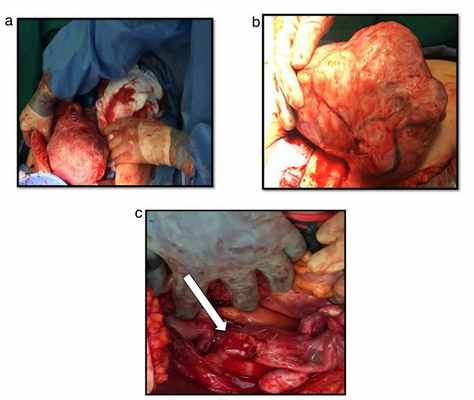

А) Сагиттальная компьютерная томография. Лейомиома «с ножкой» (стрелка), соединенная с полимиоматозной маткой.

В) Некротическая миома на ножке с полным перекрутом (стрелка).

С) Общий вид поверхности разреза лейомиомы «на ножке» (вверху) и матки (внизу).